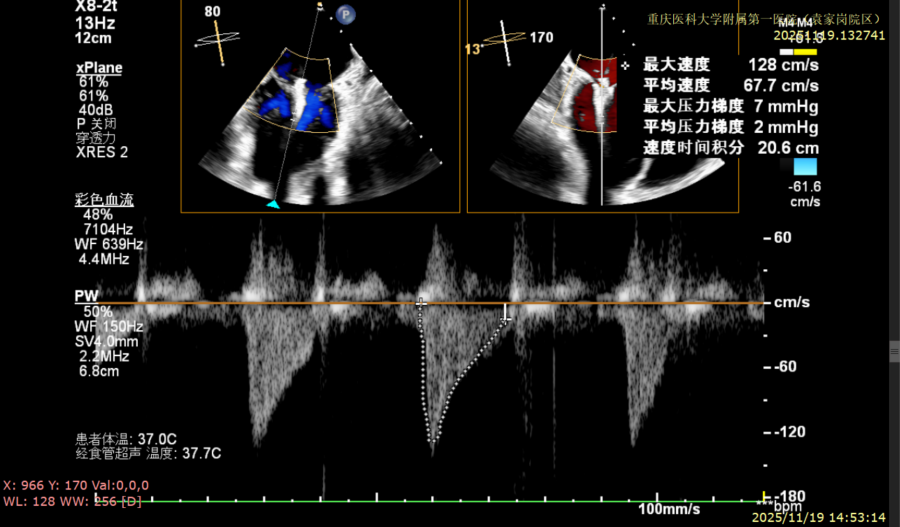

患者全麻下行TEER手术。向睿副主任团队穿刺患者右侧股静脉,在X线及食道超声指导下完成房间隔穿刺(视频4)成功获得3.95cm穿刺高度(图4)。再将加硬导丝送至左上肺静脉,20F股静脉扩张鞘充分扩张股静脉穿刺部位,沿加硬导丝将可操纵导引导管(SGC)送入左房。延SGC送入XTR夹子完成骑跨,使用M旋钮使夹子指向二尖瓣(图5)(视频5)。调整Mitraclip输送系统顺利到达二尖瓣目标位置,TEE指导下左房内完成弹道测试和Orientation调整(视频6)。缓慢将XTR夹子送入左室,并三维再次确认夹子轴向和反流位置,缓慢上提夹子使夹臂成功捕获瓣叶(视频7),Gripper Down夹持前后瓣叶并缓慢关闭夹臂(视频9),夹持后反流降至微量(视频10),二尖瓣平均跨瓣压差2mmHg(图6)。评估后将夹子释放。释放后反流微量夹子稳定。术后复查超声证实夹合组织充分,显示微量残余分流。术后二尖瓣平均跨瓣压差2mmHg,肺静脉多普勒波形恢复正常。手术时间持续约1.5小时。

图6:平均跨瓣压差2mmHg